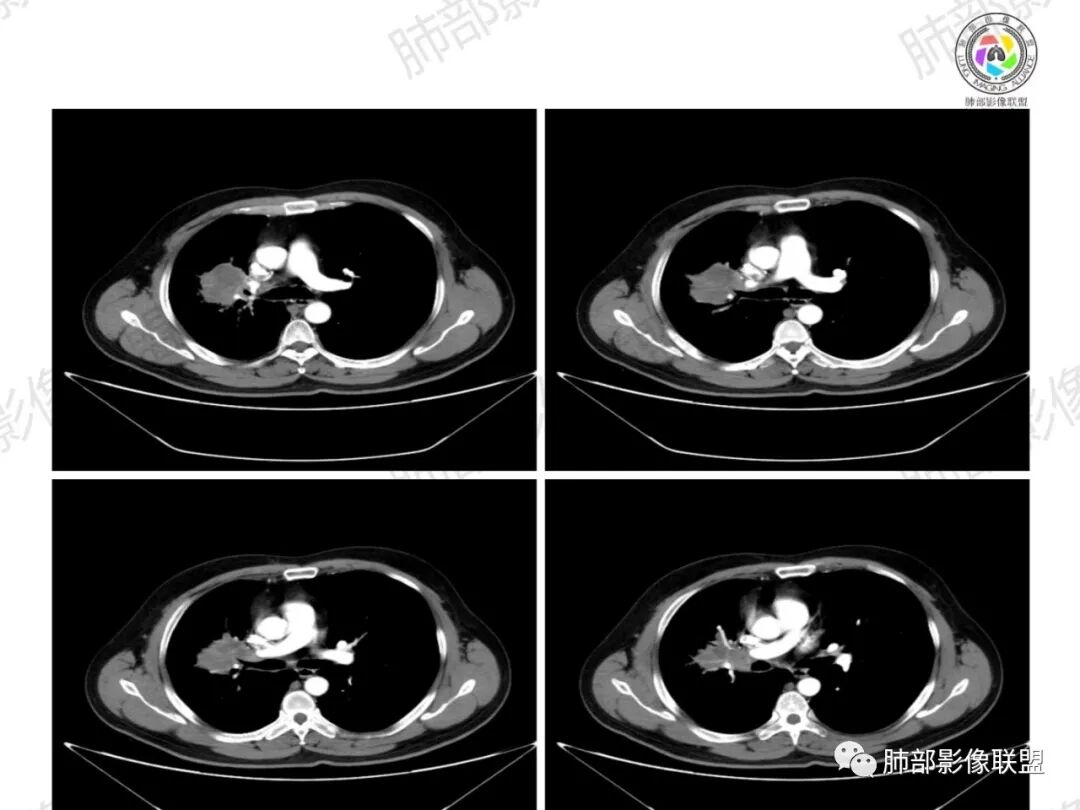

了:中年男性,右肺门肿块影,浅分叶,周围晕征,边缘清楚,小叶间隔增厚,树芽征,支气管截断,不均匀强化,内可见低密度坏死,纵隔淋巴结肿大,综合考虑肺部肿瘤并阻塞性肺炎

一切∮随缘:右肺门肿块影形态不规则,边缘毛糙,右肺上叶支气管堵塞,病变跨叶生长,远端血管束增粗,周围散在多发结节,部分位于胸膜下,平扫密度尚均匀,增强后不均匀强化,呈中度强化,坏死区无强化,纵隔淋巴结肿大。临床无感染症状,考虑恶性,鳞癌,腺癌,鉴别慢性脓肿。

那个人:中年男性,右肺肿块影,支气管截断,截断口非圆盾,病灶膨隆分叶,坏死,强化。病灶内血管破坏。病灶远端树芽及小结节影,考虑恶性,鉴别结核

周太狼:中年男性,吸烟史,陈旧结核史,呼吸道症状未提及,抗感染治疗无效。影像见右上肺门区软组织肿块影,浅分叶、毛刺,支气管似有截断,其内密度不均匀,不均匀强化,内可见低密度坏死区,病壮周围见斑片、结节影。纵隔内淋巴结稍肿大,首先考虑恶性,肺部肿瘤并阻塞性肺炎,肺鳞癌可能,鉴别结核。

弹指之间:中年男性,结核史、吸烟;右肺门肿块,特点:右肺上叶尖、前段支气管狭窄、部分阻塞(肿块大、支气管狭窄闭塞相对轻),肿块内血管部分残留(生长速度快,浸润>破坏),周围见渗出、炎症,部分实变;内见坏死、位于边缘区域;纵隔淋巴结肿大;考虑恶性,1.非支气管粘膜起源首先考虑,淋巴瘤?(但坏死相对多了);2.鳞癌(支气管阻塞轻);3.小细胞待排。